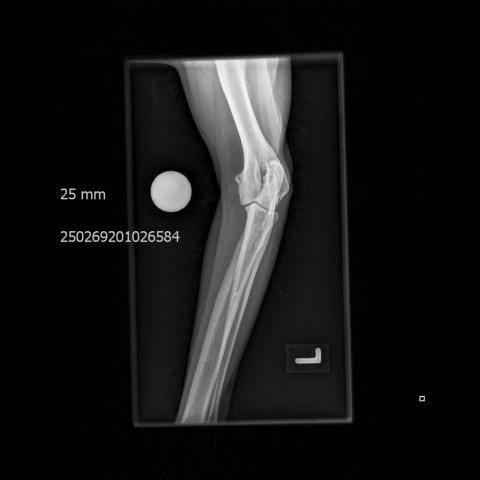

• ED Abklärungen

• Frakturbeurteilung